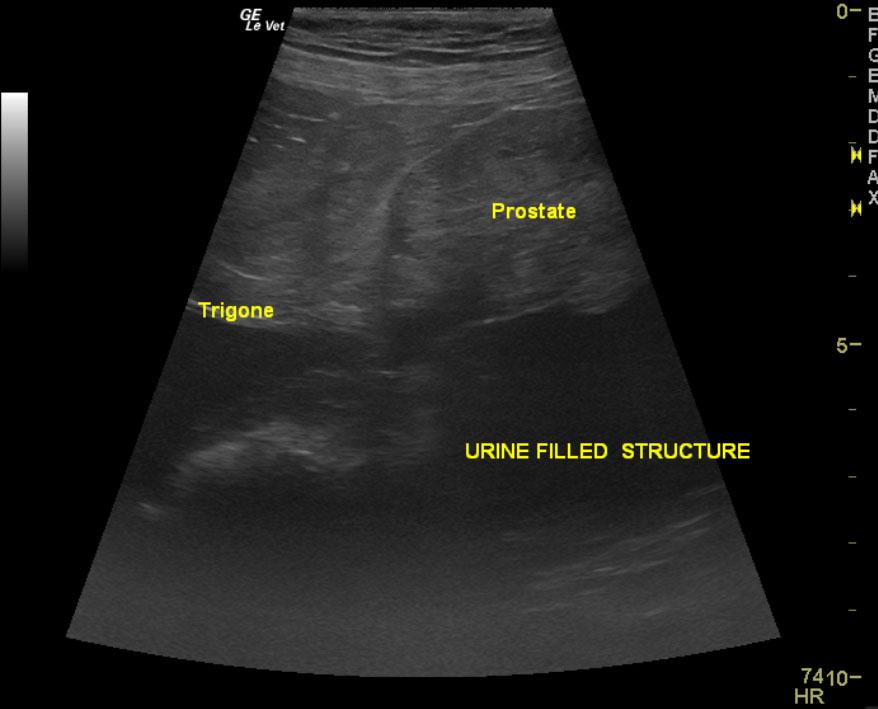

A ten year old intact male labrador retriever was presented with an enlarged prostate and painful rear end. Serum biochemistry and CBC were within normal limits. The urine specific gravity was 1.022 with mild pyuria.